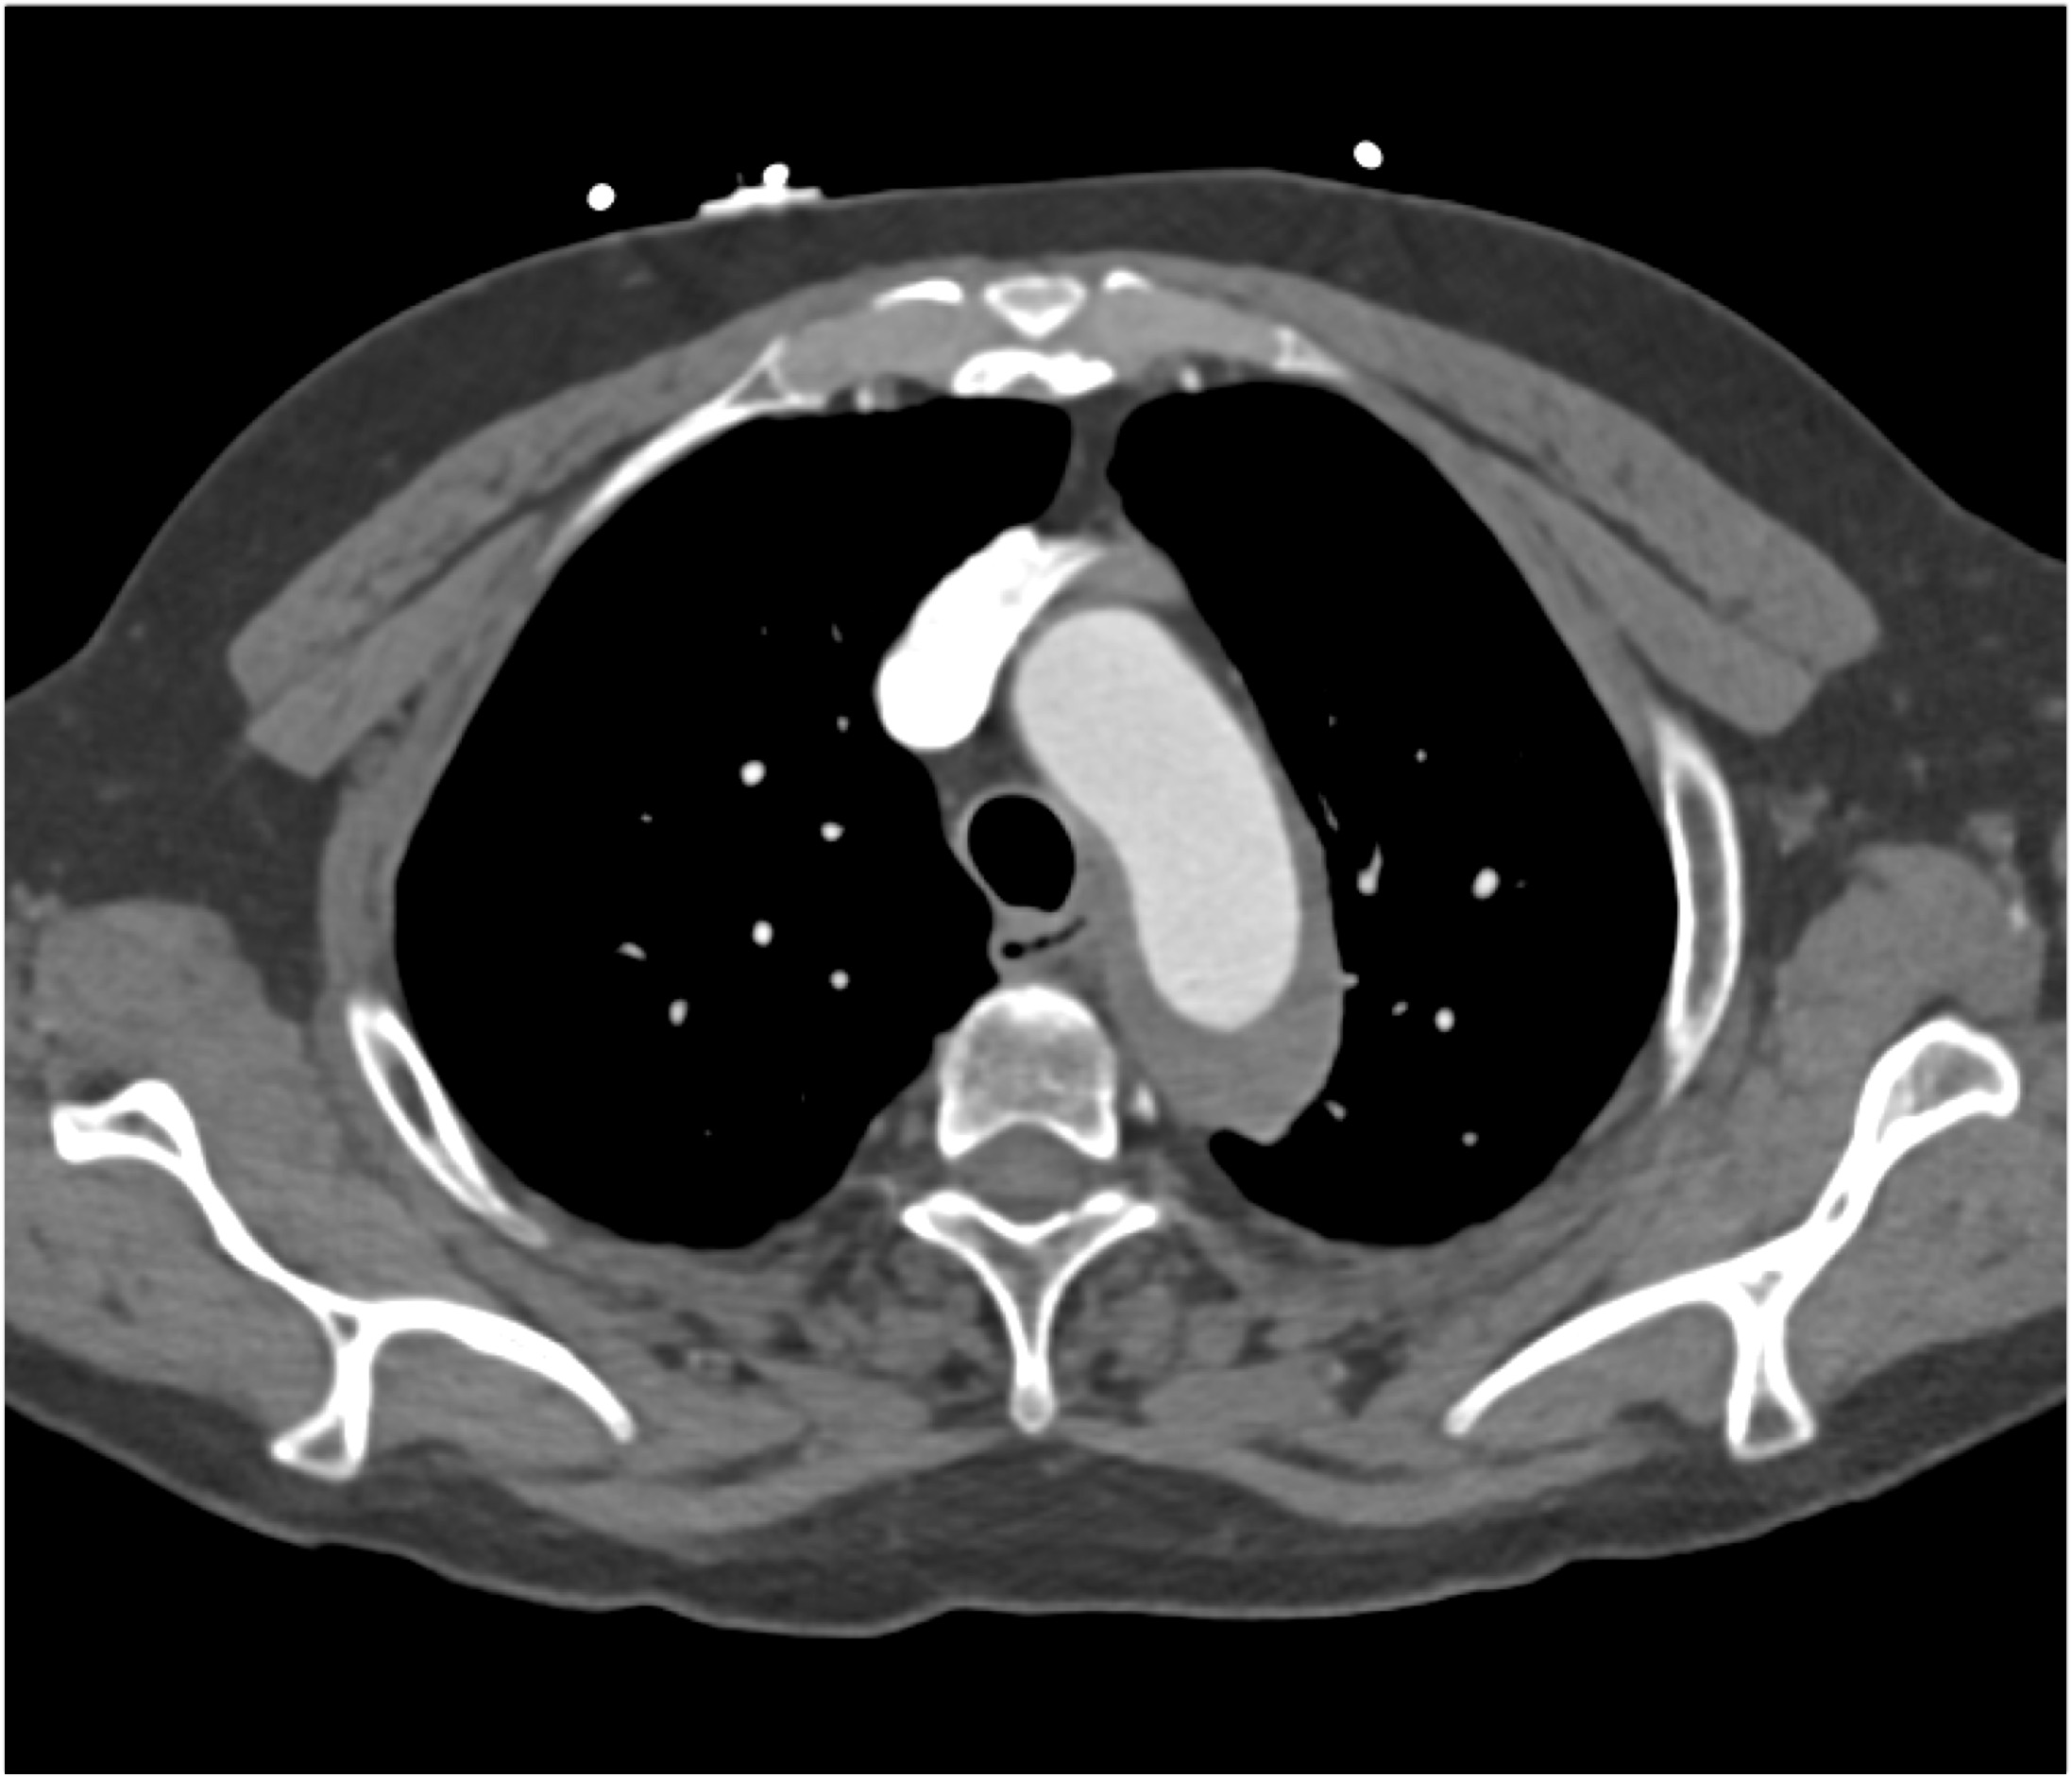

In this patient with acute back pain the best diagnosis is?

aortic dissection

intramural hematoma

atherosclerotic disease

vasculitis